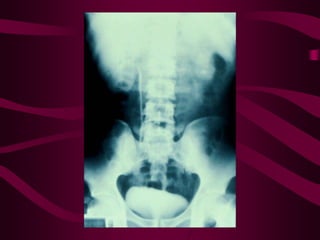

Este documento describe la tuberculosis genitourinaria. Afecta más a hombres que a mujeres. Se transmite principalmente a través de la infección pulmonar primaria y luego se disemina a través de la sangre a los riñones u otros órganos. Causa lesiones como granulomas y necrosis si no se controla, lo que puede provocar complicaciones como abscesos e insuficiencia renal. Se diagnostica mediante pruebas de orina y tratamiento con medicamentos durante varios meses.